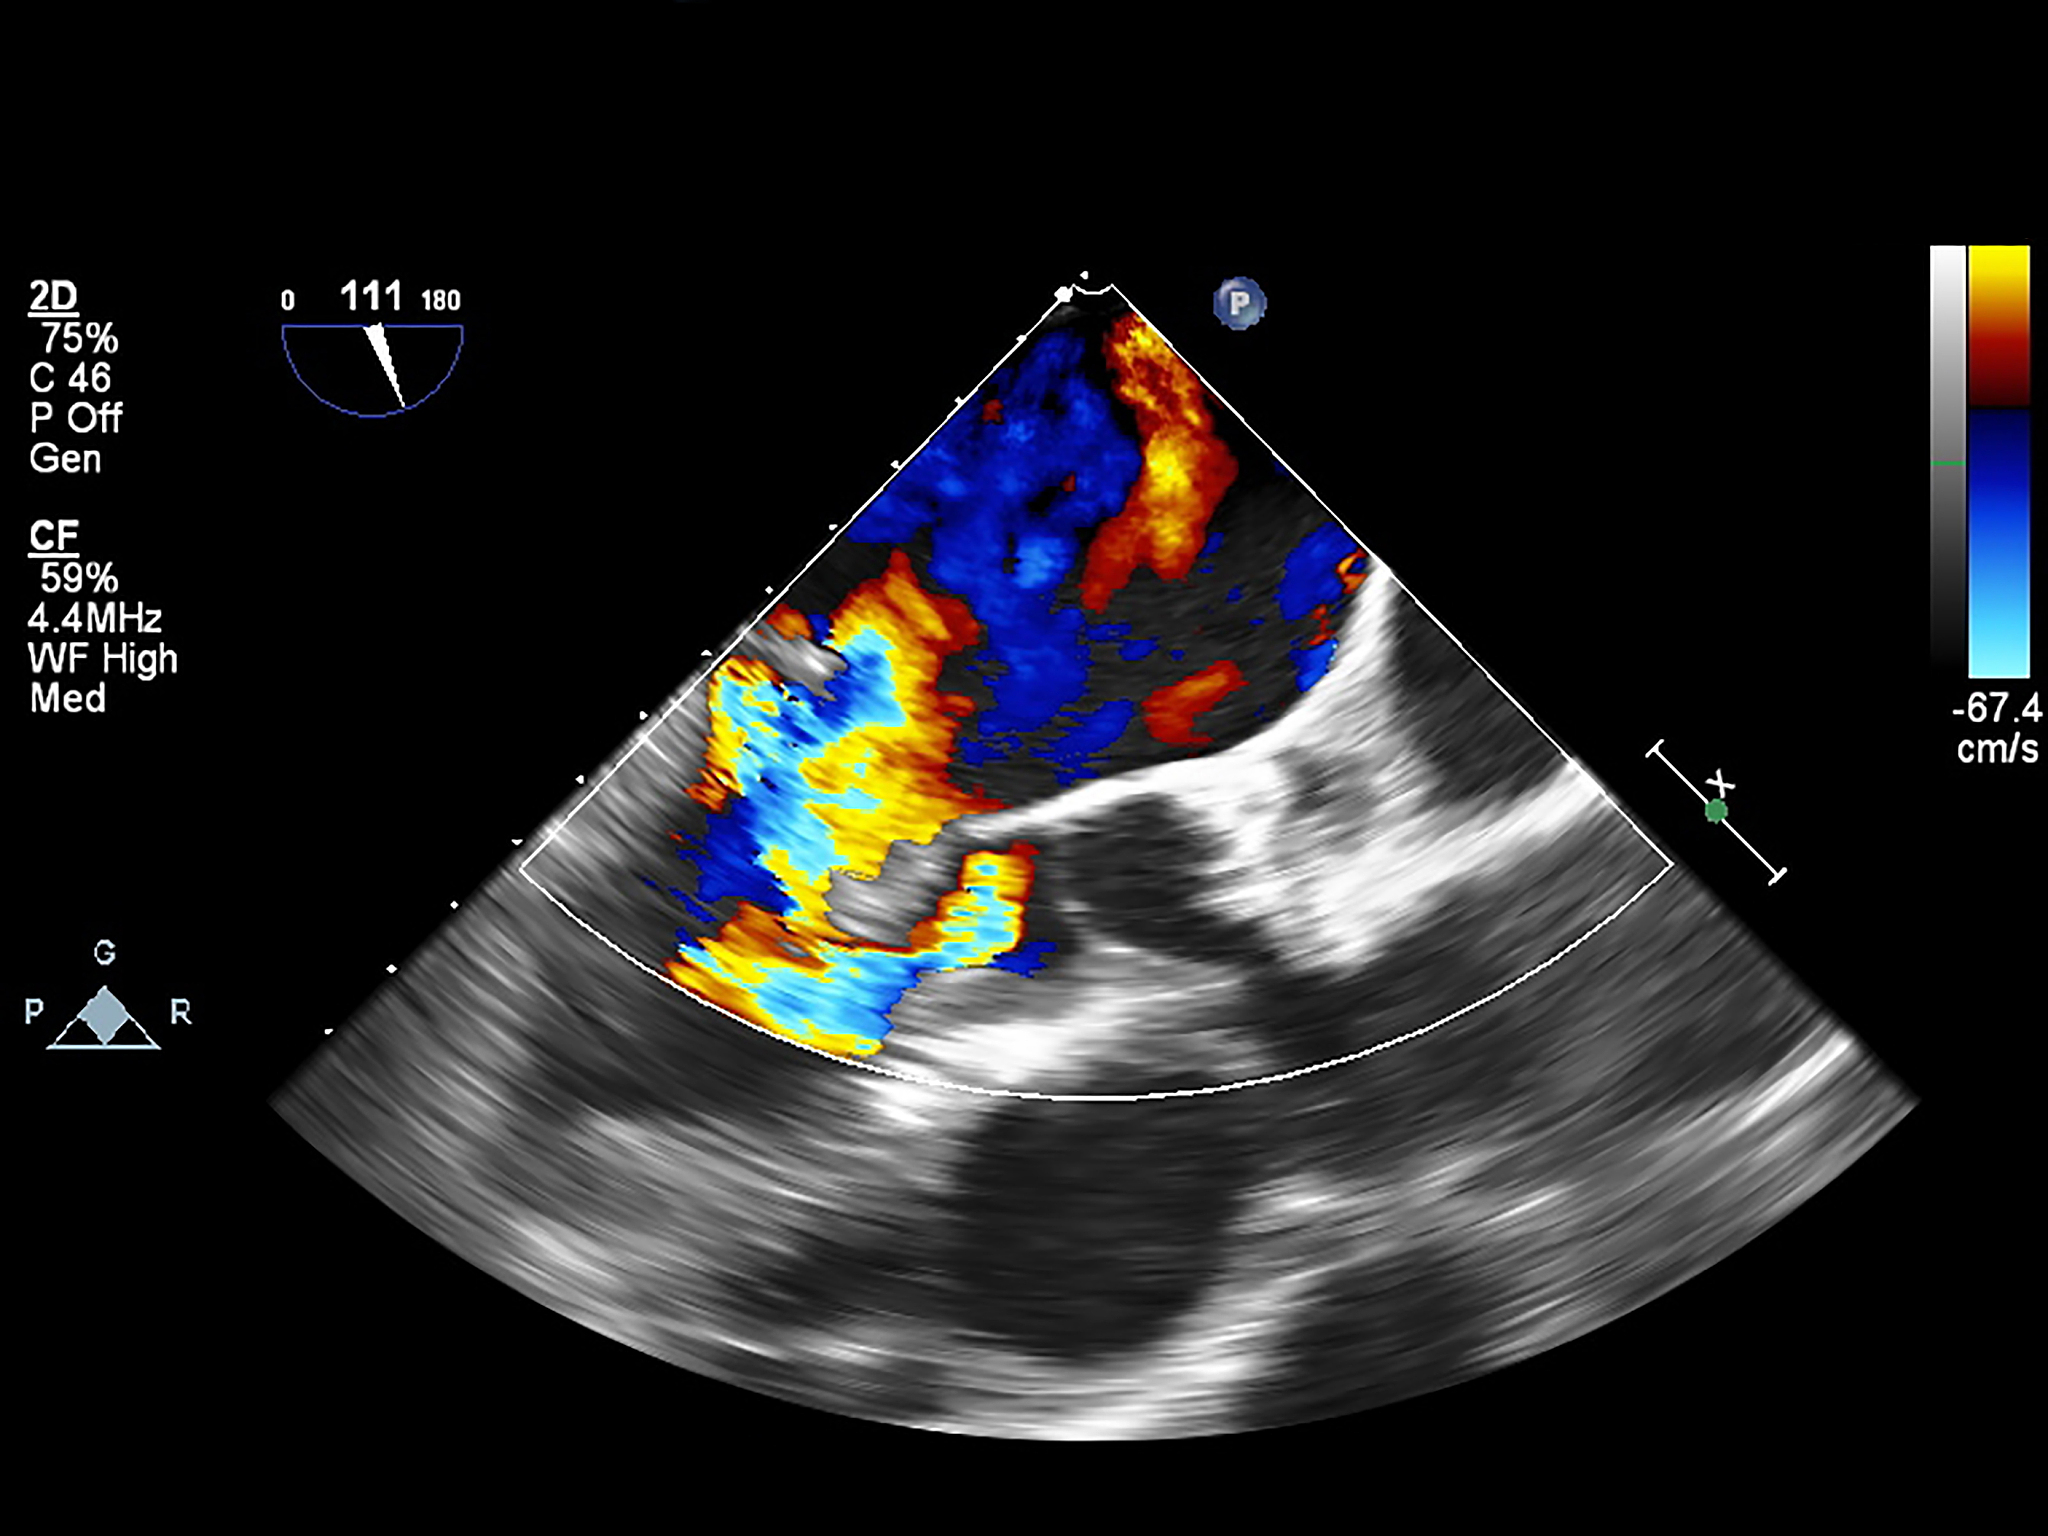

超声造影评估新生血管生成与巨噬细胞浸润的相关性

超声造影技术显示,新生血管生成的分级与巨噬细胞浸润区域的大小呈正相关。这意味着,随着新生血管生成程度的增加,巨噬细胞浸润的范围也会扩大。这一发现表明,超声造影可以作为一种潜在的非侵入性工具,用于评估炎症和组织修复过程中新生血管生成和巨噬细胞活性的关系。